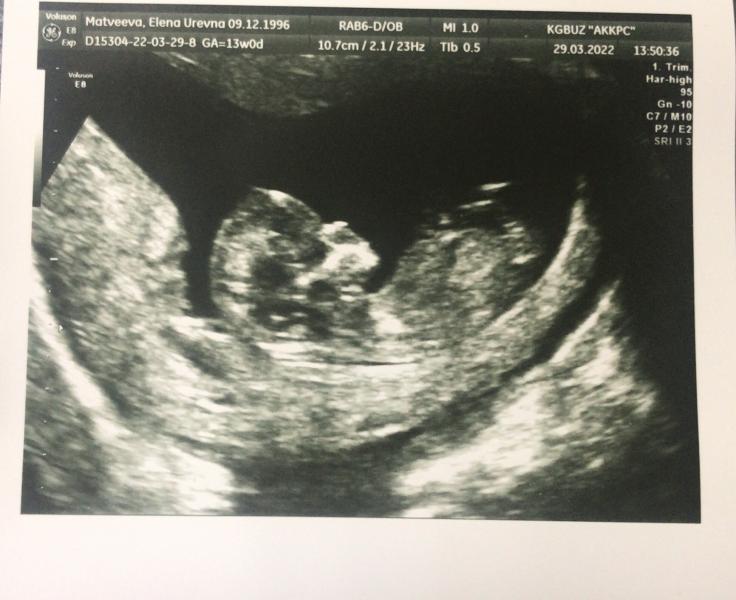

29.03.2022 ❤️

Прошла первый скрининг❤️❤️❤️

Все хорошо по узи и по крови

Срок по узи 12 недель

Акушерский 13 недель

Пдр поставили на 11 октября